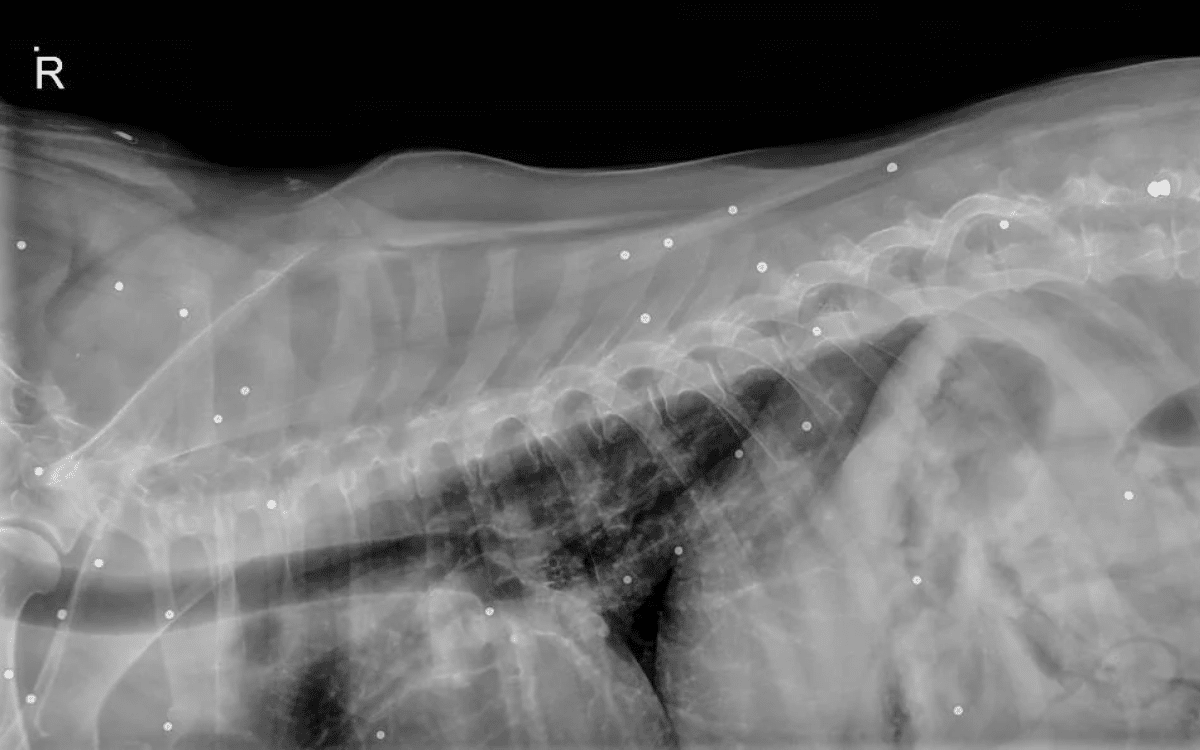

The subsequent X-rays not only revealed Momo was suffering from arthritis and hip dysplasia, but also something else.

Momo went in for a routine X-ray.

Momo had an X-ray after experiencing “mobility issues.” The results revealed something disturbing.

The X-rays highlighted a series of small dots throughout her body along with a more significant object “in her hip near her spine.” That object was a bullet, while the small dots were birdshot.

At some point before Momo came into Charlie’s care, she had been shot several times.

Thankfully, the birdshot and bullets were causing Momo no pain, but Charlie acknowledges the bullet was “pretty close” to his dog’s spine. A little closer and she might not have been here today.

Though the vet treating Momo didn’t have any theories, Charlie found plenty of people willing to weigh in on what happened after he posted pictures of the X-ray to Reddit.

Momo the dog's X-ray results.

Momo’s body was littered with small pellets. He was likely shot with a BB gun and potentially something else even worse.

“The vet didn’t have any theories, but some of the comments on the post have guesses. The small dots could be BBs from many repeated shots, or pieces of buckshot/birdshot from one blast,” he said. “The ‘bullet’ in her hip near her spine is actually a field pellet from an air rifle.”

As to how Momo ended up being shot, theories range from the seemingly logical to the more dark and disturbing. “Some people guessed it could’ve been a farmer trying to scare her off their land, others thought it might be some kid using her for target practice,” Charlie said.